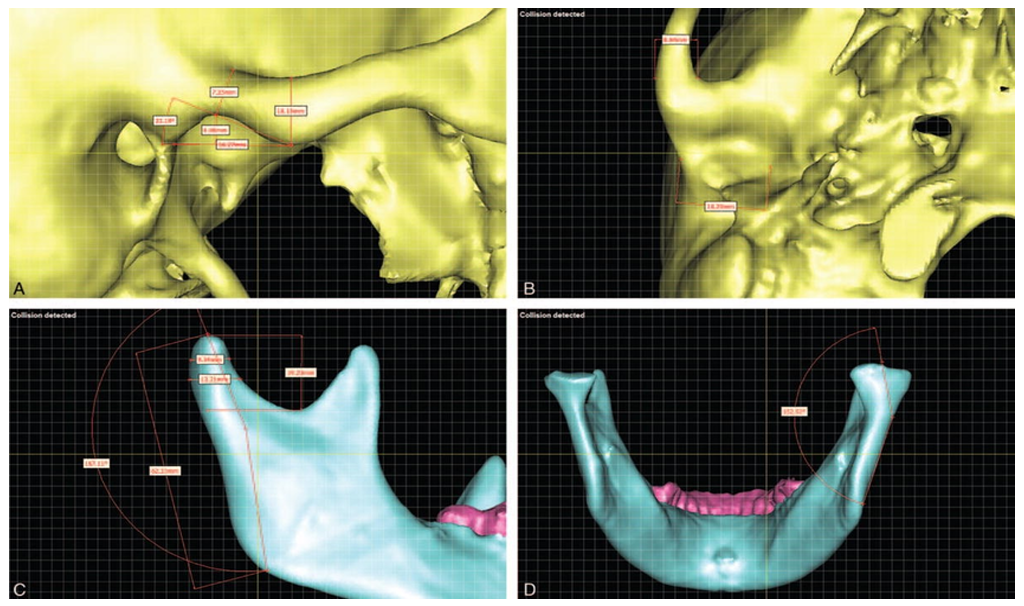

TMJ Scan

investigations are of paramount importance in the diagnostic assessment of a patient with TMD. Bony changes in the TMJ like flattening, sclerosis, formation of osteophytes,